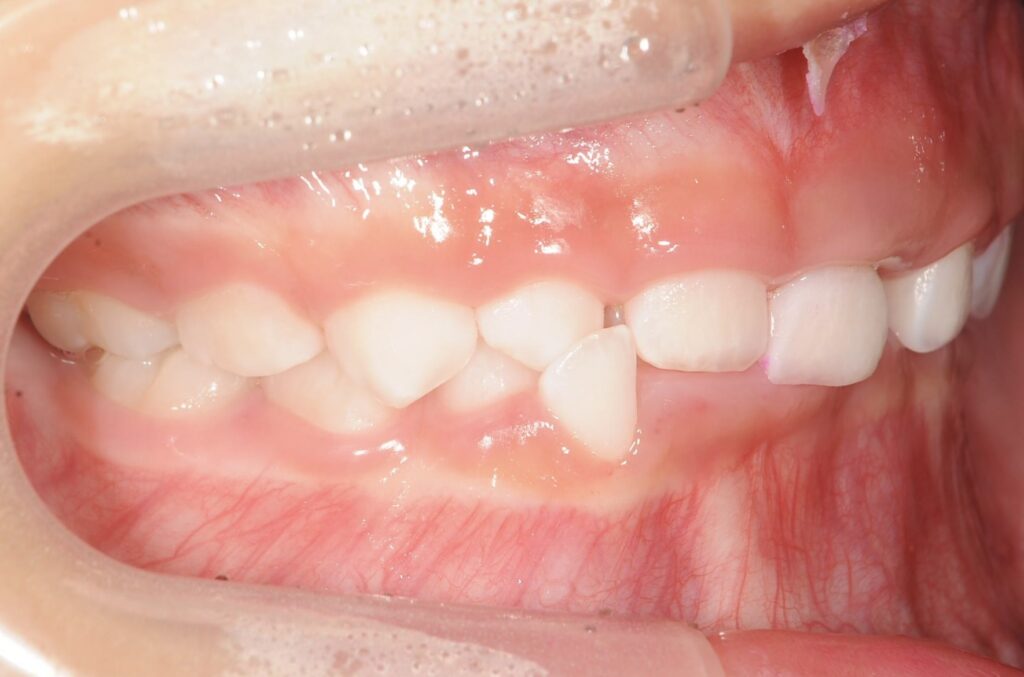

AFTER

治療内容

上下の歯並びの幅を拡げつつ、前歯の関係を改善しました。

使用装置

急速拡大装置

リンガルアーチ

機能的矯正装置(マイオブレース)

抜歯部位

抜歯なし

治療期間

2年 + 後戻り止め期間(5年)

通院回数

25回

費用

50万円程度(税別)